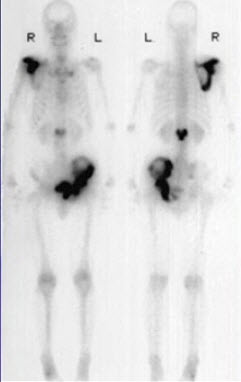

251、多项选择题

男,67岁,诉全身多处疼痛4月余,行全身骨显像如图。对此影像的描述下列正确的有()

A.有严重的骨质疏松

B.正常的骨影像

C.有双轨征

D.提示原发病可能为肺癌

E.提示患者有慢性肺部疾患